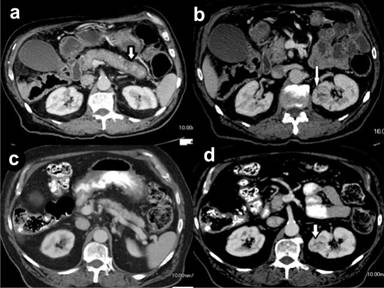

The patient was started on Prednisone 40 mg/day which led to complete resolution of his symptoms within two weeks. The dose was decreased by 5mg every week until it reached a 10mg/day as a maintenance dose. Repeat ERCP two months later for stent removal revealed a patent common bile duct. A follow up contrast enhanced CT scan was performed 5 months later to re-evaluate the renal mass which was initially suspected to be an extra-pancreatic manifestation of AIP. It revealed a normal sized pancreas, however, the contrast enhancing renal mass had increased in size to 34x30 mm (Figure 1ab). The patient underwent partial nephrectomy and was found to have primary renal cell cancer.

Figure 1. a. Contrast enhanced axial CT of the abdomen shows enlarged pancreas with loss of normal fatty lobulation. There is a hypodense "halo" or capsule (white arrow) around the pancreas. b. Contrast enhanced axial CT of the abdomen showing a well circumscribed solid heterogonous renal mass measuring 30x26 mm in the mid pole of the left kidney. c. Contrast enhanced CT of the abdomen 5 months later showing resolution of pancreatitis and a normal appearing pancreas. d. Contrast enhanced CT scan 5 months later showing the enlarging renal mass 34x30 mm. |

Renal mass is one of the extra-pancreatic manifestations of IgG4 related disease which could range from tubulointerstitial nephritis to nodular lesions and pseudotumors mimicking renal cell carcinoma [5]. On radiological evaluation using contrast enhanced CT scan; the most common renal abnormality in IgG4 related disease was multiple low density lesions [6]. However, mass like lesions simulating renal cell carcinoma have been recognized in 3-27% patients [6, 7]. In the past, a number of such patients with renal masses underwent nephrectomies [8], which later revealed a dense lymphoplasmacytic infiltrate with an increased number of IgG4 positive plasma cells on pathological examination. Histologically, such renal lesions are characterized by an irregular pattern of fibrosis called storiform fibrosis which is considered to be pathognomonic for renal manifestations in IgG4 related disease [9]. Lately, CT guided renal biopsies have been performed in such cases, thereby preventing nephrectomies [10]. Being a rare clinical disorder, no formal guidelines evaluating the role of renal biopsy in such cases have been formulated (Figure 1cd).